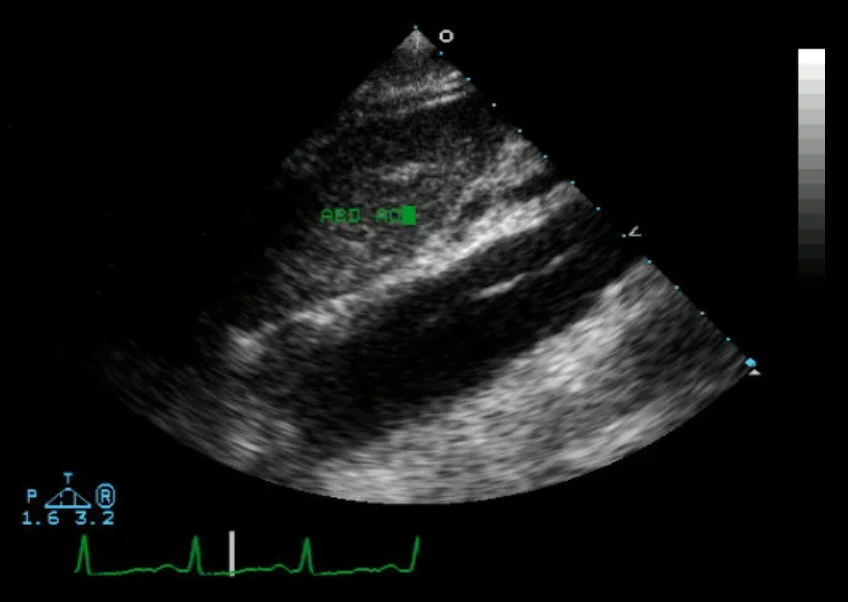

- TTE

- Sens: 77-80%

- Spec: 93-96%

- For ascending aorta only

- In hands of experienced operators

- Suprasternal view: put the US in the juglar notch, aim down